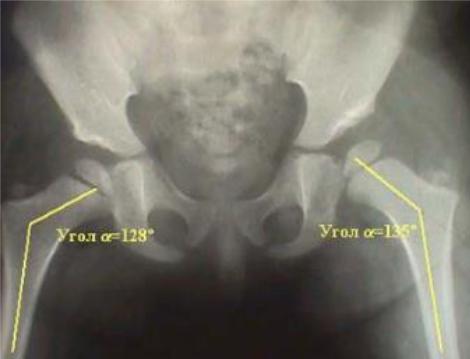

Шеечно-диафизарный угол (инклинация шейки бедра) - угол пересечения продольной оси диафиза с осью шейки бедра.

Существуют возрастные, половые и индивидуальные различия в величине нормального ШДУ. В среднем нормальный ШДУ: у взрослых126-

130°, у маленьких детей144°, у стариков120°.

В норме истинный ШДУ составляет от 125° до 135 градусов.

При врожденном вывихе бедра, как правило, ШДУ вальгизизирован и составляет более 135 градусов.

Рис. 80. Истинный ШДУ